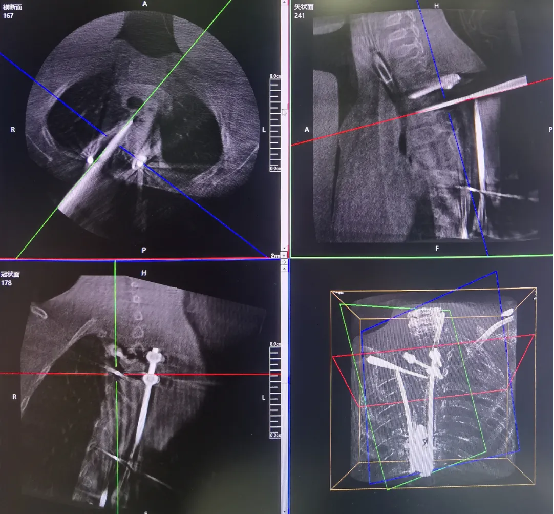

The combination of three-dimensional imaging and a surgical robot effectively addresses the critical challenges of complex anatomy and the need for high-precision localization. This synergy enables visualized preoperative planning, sub-millimeter intraoperative positioning accuracy, and a significant reduction in surgical risks.

The 3D C-arm performs image acquisition and 3D reconstruction.

Robot-assisted screw insertion path planning

Robot-assisted precise precise screw placement.